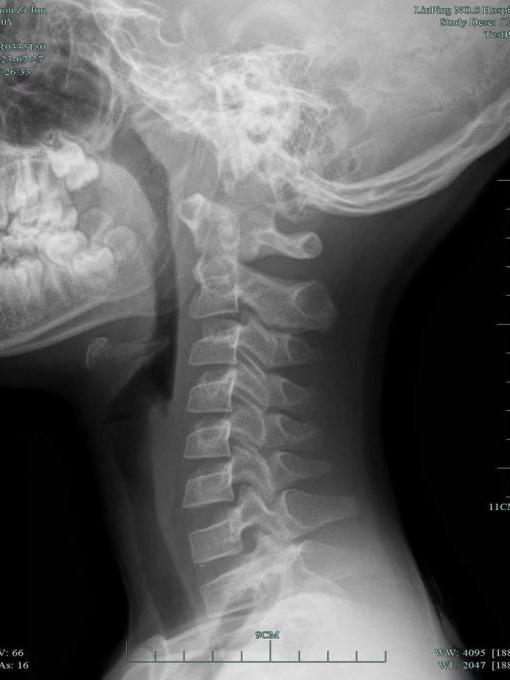

王主任查看小杰的颈部DR片惊讶地吐出四个字:一塌糊涂!

小杰颈椎病变严重,小关节错位,颈椎反弓。明明才10岁,颈椎已经跟30岁的人一样,老化程度甚至超过不少接诊的成年人。

一般这种程度的颈椎病,很难在小孩身上看到,患者以长时间对着电脑办公的白领居多。最关键的是,这种伤害是不可逆的。治疗只能得到改善,也就是说,颈椎病将伴随小杰终生!